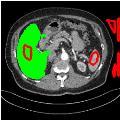

To test the generalizability of SAM-Mix, we validate it on a cross-domain dataset (TotalSegmentator). As reported in Table 2, the segmentation performance of SAM-Mix on the cross-domain task is as promising as the in-domain results. Despite the data shifts, from LiTS to TotalSegmentator, SAM-Mix outperforms all of the baseline models in terms of generalizability, by significant margins. SAM-Mix-50 achieves a Dice score improvement of 25.4%, and a lower Hausdorff distance by 62.26% compared to the best-performing full-supervised U-Net model. These results further validate the few-shot capabilities and establish our SAM-Mix as a well-generalized tool for medical image segmentation.